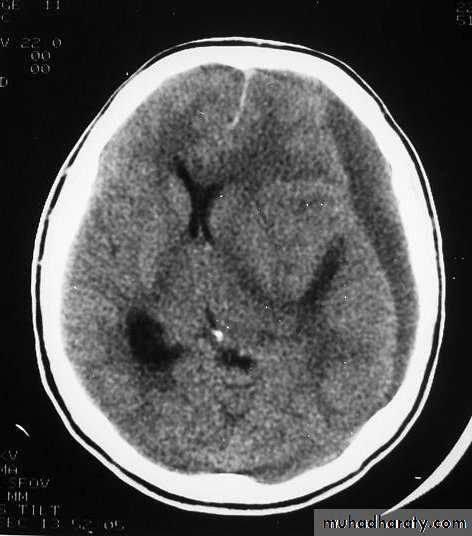

Chronic Subdural Haematoma

Most common in infants and in adults over 60 years of age secondary to SLIGHT blow to the head which may pass unnoticed.

Source of bleeding (haematoma): usually from bridging veins as they pass to the venous sinuses.

The patients present with progressive neurological deficits more than 3 weeks after the trauma.

The initial head injury is often completely forgotten.

CT scan: the acute clotted blood is initially appears white (hyperdence), but as it liquefies, it slowly becomes black (hypodense).

They should be drained if they continue to enlarge.

They are evacuated by drilling burrholes over the collection and washing it out with warmed saline.